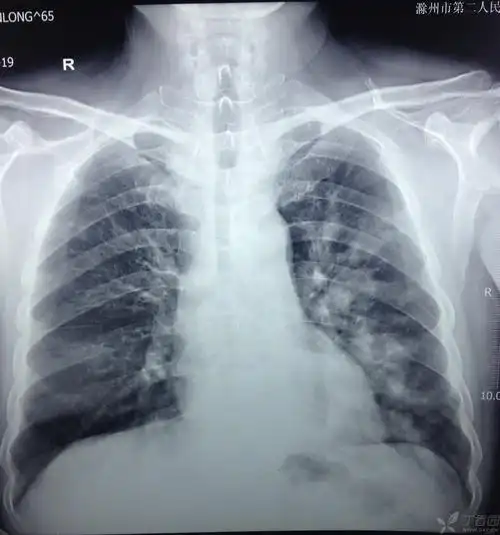

病毒性肺炎的影像学表现

支原体肺炎影像分析

【病例讨论】重症肺部感染一例 [病例帖]